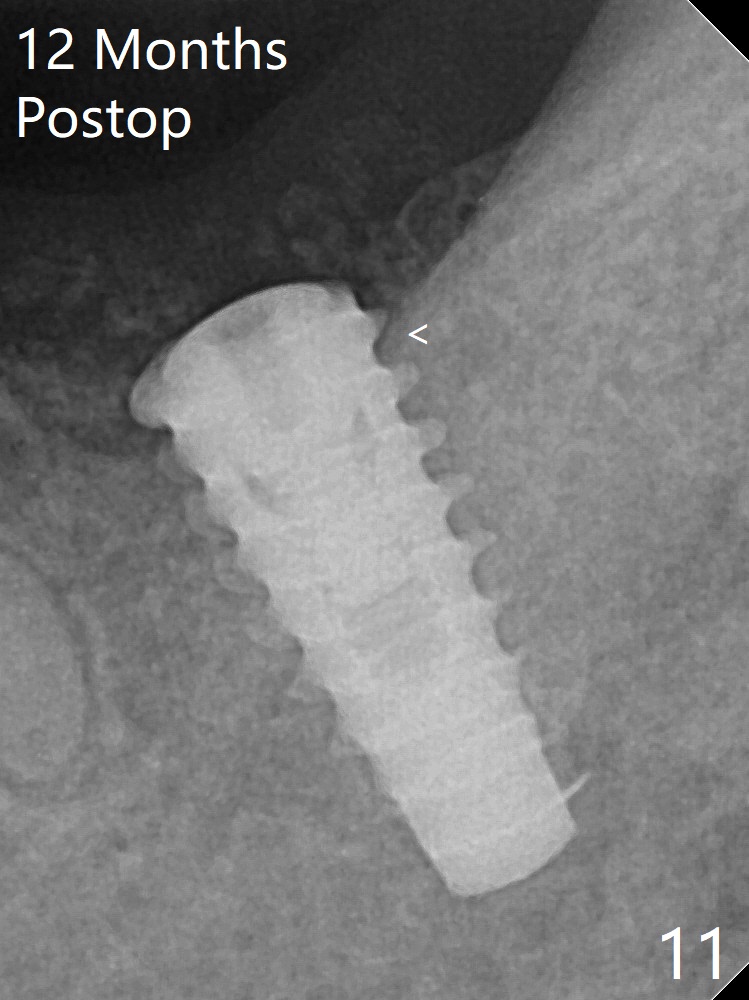

The implant is removed, cleaned with Titanium brushes and H2O2 in vitro and repositioned 12 months postop (Fig.14: arrow (gaps: post granulation tissue removal)). The gaps are regrafted with sticky bone and covered with PRF membrane and Cytoplast.取出植体,钛刷清洗,即刻植入,种深些(图十四:箭头),冠部螺纹两旁有间隙(*);放置愈合帽,最后表浅放置粘性骨粉(图十五:*)。覆盖不可吸收膜,